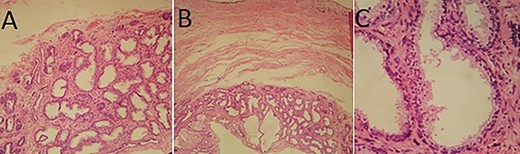

In pathological examination, the gross pathologic specimen was a 10 × 9 × 4 cm mass containing multiple varied-size cysts. Histologically, the tumor was composed of acini, dilated glandular structures and cyst lined by prostatic-type epithelium set in a hypocellular stroma. No atypical features or mitosis was noted in neither the glandular nor the stromal components of the mass (Fig. 5). These lesions matched with a multilocular prostatic cystadenoma.

Pathological examination: (A and B) cystic wall containing numerous acini and dilated glandular structures (HES×10 and ×4); (C) Acini and cysts lined by prostatic-type epithelium (HES×20).